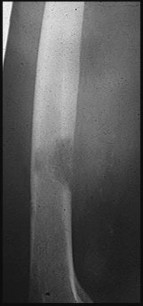

Question 2:

A 12-year-old boy presents with left thigh pain, an antalgic gait, and an externally rotated left lower extremity. Radiographs demonstrate the pathology shown. Which of the following is considered an absolute indication for prophylactic pinning of the asymptomatic, contralateral hip in a patient presenting with Slipped Capital Femoral Epiphysis (SCFE)?

Correct Answer: Underlying endocrine disorder (e.g., hypothyroidism)

Explanation:

SCFE is characterized by a displacement of the proximal femoral epiphysis. Prophylactic pinning of the contralateral hip is somewhat controversial but generally recommended in patients with a high risk of subsequent contralateral slip. Absolute indications or highly strong recommendations for prophylactic contralateral pinning include an underlying endocrine disorder (such as hypothyroidism or growth hormone deficiency), renal osteodystrophy, previous radiation therapy, and presentation at a very young age (e.g., < 10 years). Endocrine disorders dramatically increase the risk of bilateral involvement, often occurring simultaneously or sequentially.